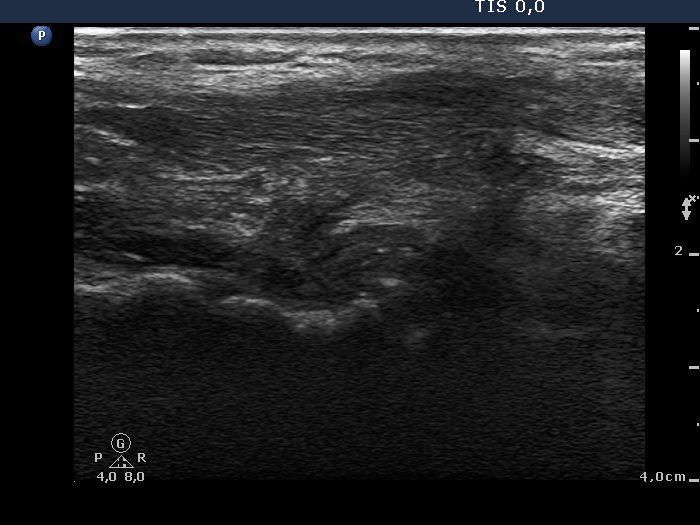

Eleven months after surgery (fourth row of images)

Ultrasonography: There was no thyroid parenchyma in thyroid beds. The regenerative mass disappeared.